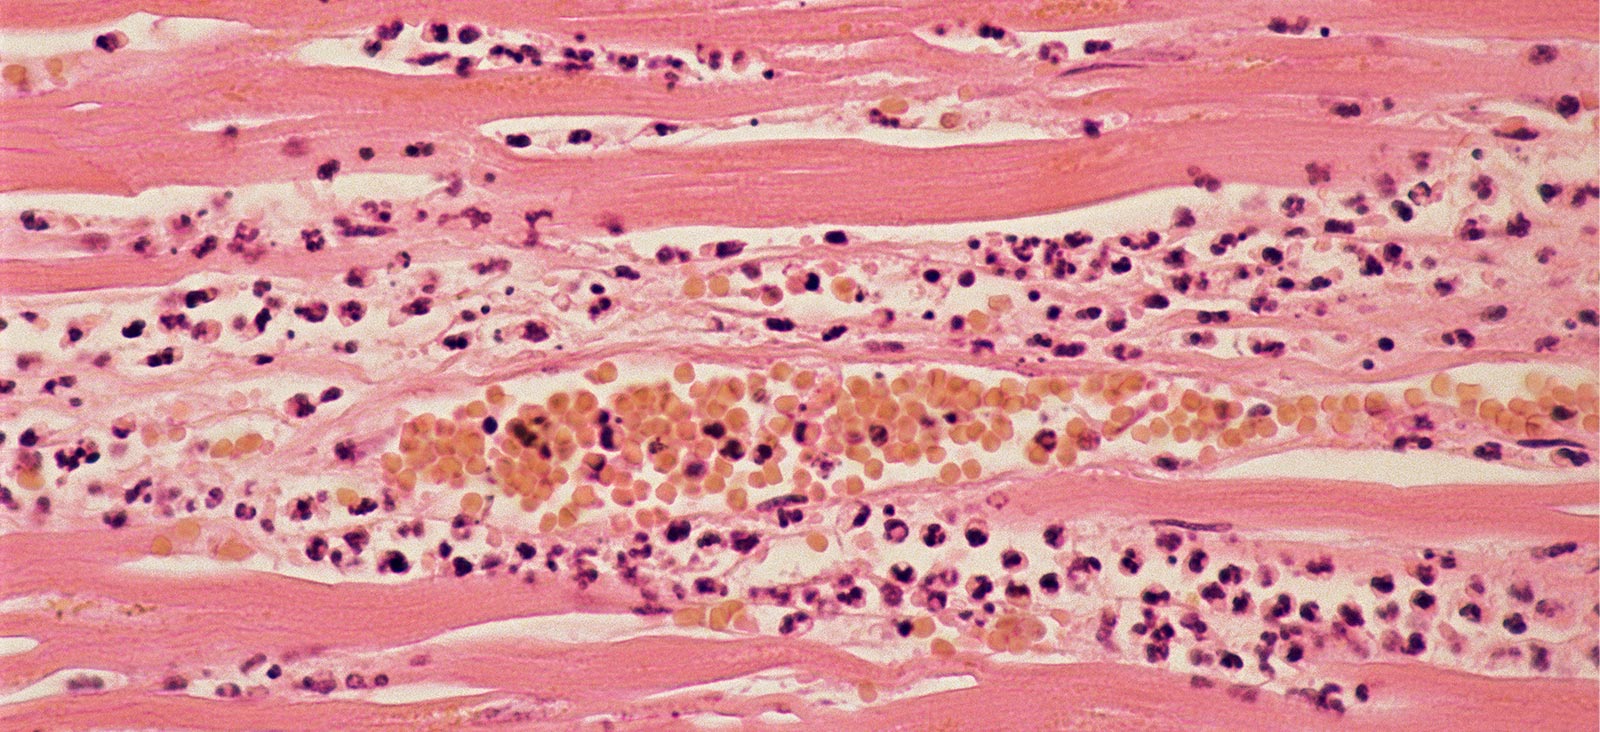

A heart attack – also known as myocardial infarction (MI) – is a severe and potentially life-threatening cardiovascular event in which the muscular layer of the heart (myocardium) is deprived of blood and oxygen for an extended period of time.